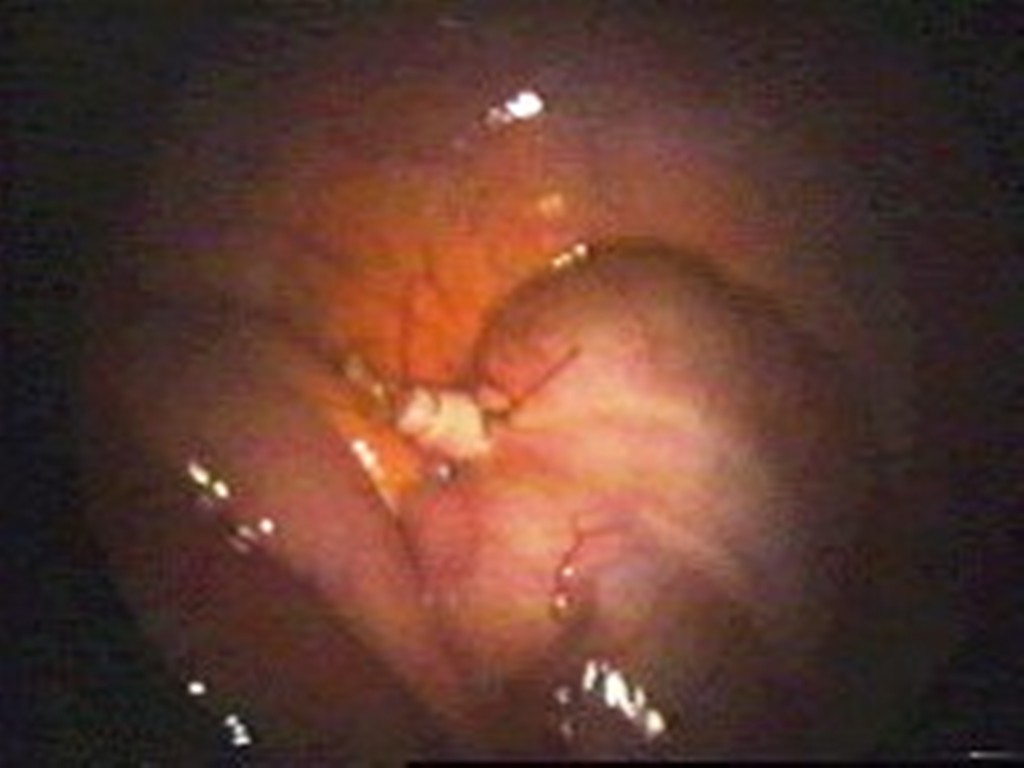

At Remedy Hospital we offer surgery for all conditions of appendix like appendicitis, appendicular malignancy, and mucocele of appendix. We offer surgery by latest technique (Laparoscopic Appendectomy) as well as time tasted conventional technique (Open Appendectomy).